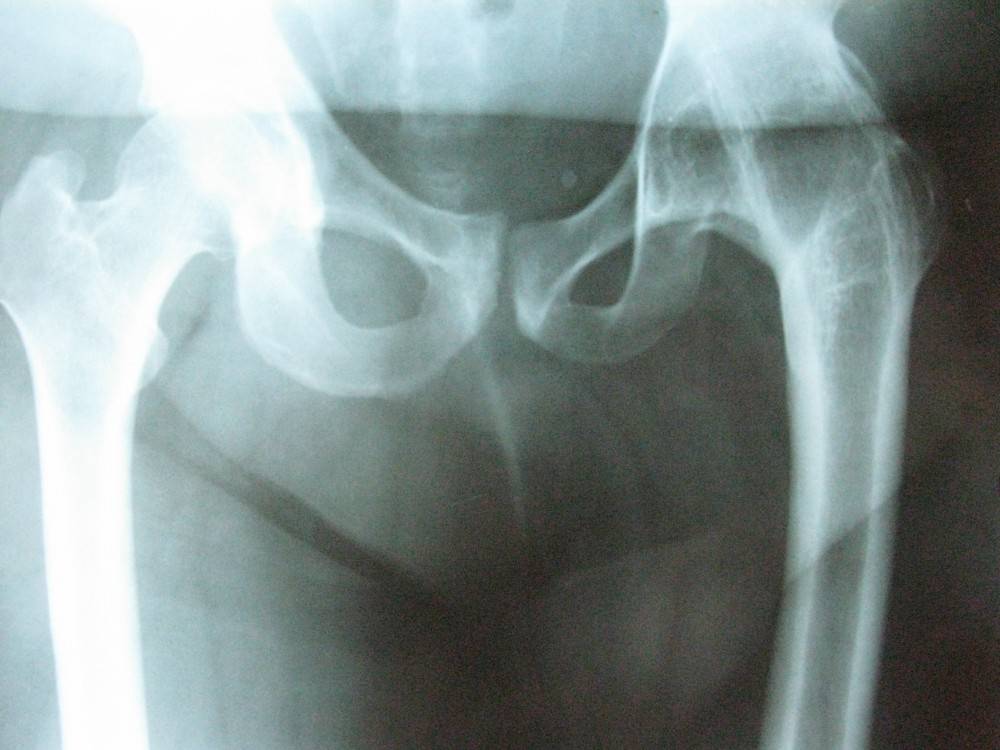

Фазы развития остеохондропатии: а — нарушение кровообращения, б — развитие некроза, в — образование фрагментов кости, г, д — восстановление, заживление кости

Остеохондропатия – внешние и рентгеновские проявления

Ткань верхней полусферы головки беда, в которой развился асептический некроз, теряет устойчивость к механической нагрузке, из-за чего даже при обычной повседневной нагрузке (ходьба, бег, прыжки) возникает ее постепенная деформация. Выраженность деформации напрямую зависит от размеров и локализации очага асептического некроза в эпифизе и может быть от практически не диагностируемой деформации на рентгенограмме до грубой «грибоподобной» или «седловидной» формы.

- I — жалобы на боль и утомляемость после ходьбы, заметно незначительное нарушение походки, наблюдаются микроскопические патологические изменения в костной ткани, а именно развивается субхондральное омертвение. Рентгенографические изменения затрагивают до 10% площади головки тазобедренного сустава. Начатое на данном этапе лечение позволяет полностью предотвратить дегенерацию тканей;

- II — появляются неприятные ощущения в тазобедренном суставе. Наблюдаются патологические переломы. От структурных изменений страдает до трети площади головки бедренной кости;

- III — длится 1,5 — 3 года, характеризуясь вялым течением. Внешние проявления болезни становятся более выраженными. Боль проявляется не только при ходьбе, но и в покое. Мышечные ткани на пораженной стороне атрофируются, амплитуда движений снижается, ребенок хромает. На снимках хорошо заметно, как головка бедренной кости буквально разваливается на фрагменты;

- IV — это восстановительная фаза болезни. В этот момент на омертвевших участках начинается нарастание костной ткани. Болевой синдром уменьшается, но амплитуда движений остается ограниченной. Скелетные мышцы пораженной конечности практически утрачивают способность к сокращению;

- V — характеризуется нарастанием костной ткани и восстановлением кости. При правильном и своевременно начатом лечении здоровье ребенка полностью восстанавливается.